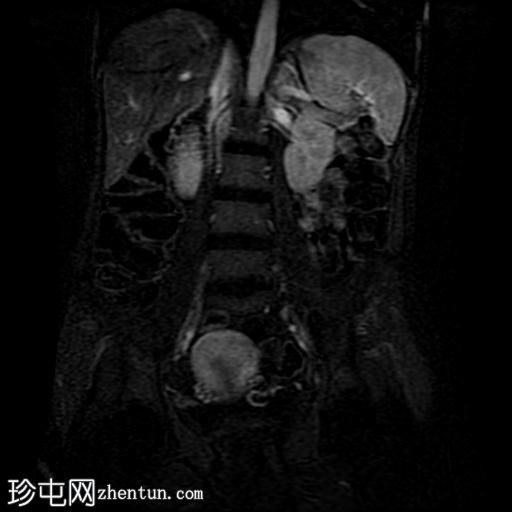

冠状位T2加权像

脂肪抑制

回肠末端及盆腔回肠肠袢可见长段肠壁增厚及强化,肠周血管丰富,呈“梳状征”,并可见明显的纤维脂肪浸润。

未见瘘管、积液、腹水或梗阻。

磁共振肠道造影(MRE)结果支持克罗恩病的诊断,显示远端及末端回肠以活动

性病

变为主,并可见明显的肠周血管。